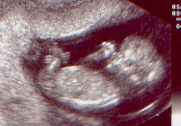

Schon etwas überraschend machte sich im Januar01 ein Krümelchen breit in Mamas Bauch, um einen kleinen Spielkameraden für unsere drei zu geben .

12.SSW